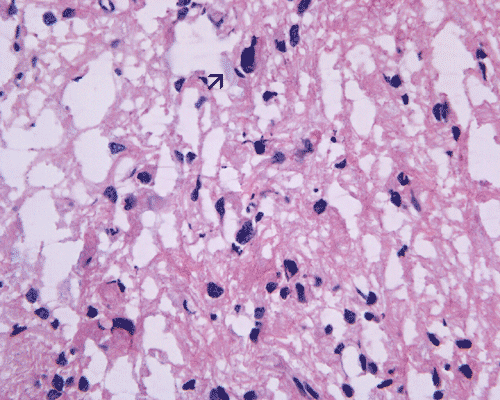

Pathology of the case: A small specimen was obtained by endoscopic biopsy. The specimen cannot be smear out after being squashed and remain as several, large, stellate-shaped cohesive clumps (Panel D). The edges of these clumps are relatively thin and allows better observations. The nuclei do not appear to be pleomorphic. Many elongated cytoplasmic processes can be seen (Panel E) and are suggest a glial nature of these cells. The lesion gives a spongy appearance on low-magnification (Panel F). On medium-magnification, there are some clustering of nuclei (Panel G). On high-magnification, the nuclei appear hyperchromatic and pointy but no substantial pleomorphism, prominent nucleoli, or mitotic figure. Some bluish, mucoid material is identified in some microcysts (Ú in Panel H).

There is no endothelial proliferation or necrosis. An  intraoperative diagnosis of glial neoplasm was made. The lesion was entirely resected. On paraffin section, the lesion has a hypocellular background decorated by many small microcysts, often in clusters, that contain mucoid material and small cluster of nuclei that resemble bundles of flowers (Panel I and J).  The nuclei are bland. There was no mitosis, endothelial proliferation or necrosis (Panel K and L).